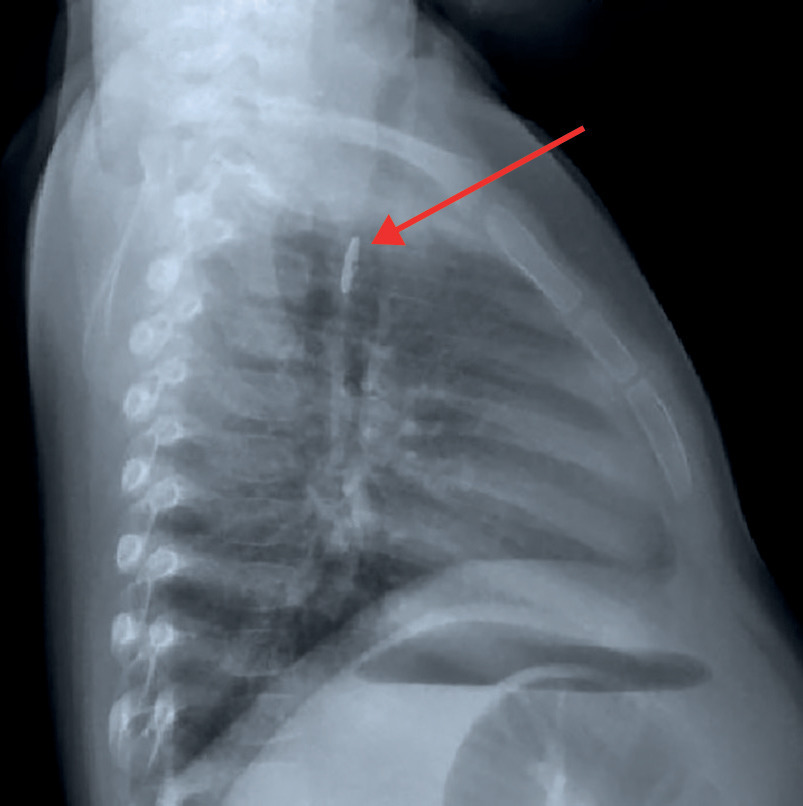

Le bilan radiologique comporte des clichés cervicaux, thoraciques et éventuellement un abdomen sans préparation. En cas de CE radio-opaque (objet métallique, pièce de monnaie...), il permet de déterminer sa taille, sa nature et sa localisation, de dépister d’éventuelles complications et de surveiller sa progression dans le tube digestif. Il n’est pas systématique en cas d’incarcérations d’aliments dans la muqueuse digestive.